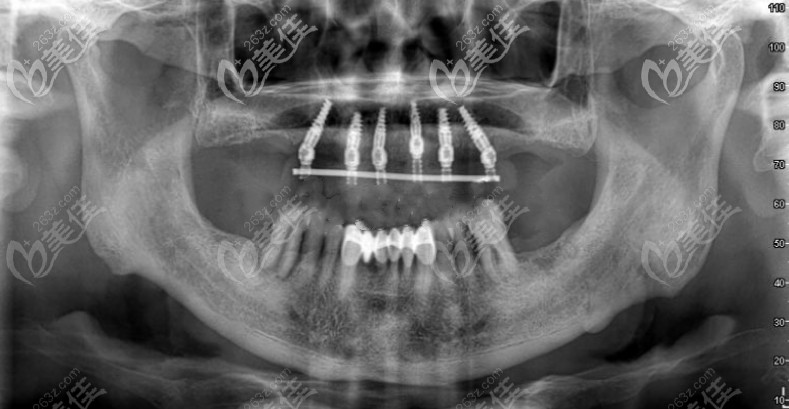

近期打算給老爸做種植牙,但不知道長沙地區(qū)的種植牙收費(fèi)情況,所以想問下:在長沙用3-6顆奧齒泰做半口即刻種植牙要多少錢?尤其像這種多顆種植的在長沙可領(lǐng)優(yōu)惠嗎?... b622 G0 V0